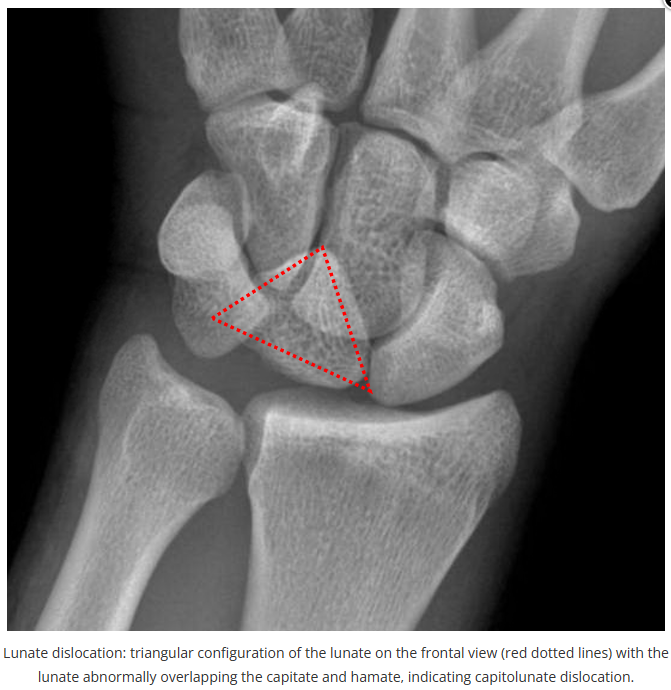

今天是腕部与手的X线片。所有X线片都

带有标注和说明

,可以选择长按图片,

自动翻译相关说明